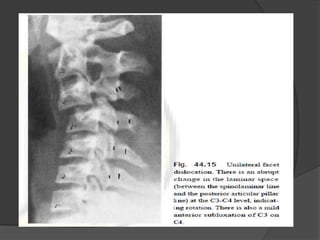

Unilateral facet dislocation

Wedge fracture

 Compression

fracture resulting from

flexion.

Flexion compression injury

 Best seen on lateral view

 Stable

 Common in

 Elderly patients

with osteoporosis or osteogenesis

imperfecta